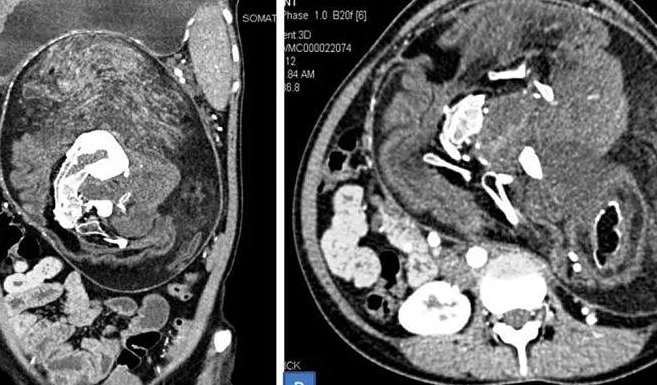

Bụng cô gái ở Ấn Độ cứ to dần và nghĩ rằng do mình béo. Nhưng thấy đâu có ăn nhiều nên đến bệnh viện khám, bác sĩ nghi có khối u, kết quả chụp CT bất ngờ phát hiện bào thai đôi.

Hai thai song sinh đã bị biến dạng song vẫn đang phát triển trong bụng cô gái 17 tuổi. Ban đầu kiểm tra, các bác sĩ không nhìn rõ bào thai. Kiểm tra kỹ hơn, họ khẳng định là thai nhi dù không hoàn chỉnh, với xương đốt sống, xương sườn và xương đùi. Ngoài ra, bào thai còn có tóc và răng, cùng những cấu trúc mô không định hình mà nếu phát triển bình thường sẽ thành những bộ phận cơ thể trẻ sơ sinh.

Bác sĩ xác định đây là hiện tượng thai trong thai, xảy ra một trong số 500.000 ca sinh sản trên thế giới. Tình trạng thai trong thai thường gặp ở trẻ trai, được phát hiện sớm và hiếm khi vượt quá thời thơ ấu. Trường hợp cô gái trẻ này được báo cáo mới đây trên Tạp chí y khoa Anh, là người đầu tiên mang thai song sinh bất thường trong cơ thể mình đến tuổi trưởng thành. Theo Viện Khoa học Y khoa All India, cô cũng là người phụ nữ lớn tuổi nhất được xác định vẫn "mang dấu tích của một song thai".

Ảnh chụp CT khối thai song sinh trong cơ thể cô gái. Ảnh: BMJ Case Reports.

Thai đôi dị dạng bắt đầu phát triển cùng với cô gái khi cô còn trong bụng mẹ, bị hấp thụ vào cơ thể của cô gái và không thể phát triển thêm nữa. Các bác sĩ lý giải, trong bụng người mẹ khi ấy mang ba thai nhi. Một trong ba thai phát triển và lấn lướt hai thai kia, khiến chúng không phát triển bình thường. Thai phát triển bình thường và đứa trẻ được sinh ra chính là cô gái. Hai thai kia không phát triển hệ thần kinh và não, nhưng vẫn sống được như "vật ký sinh" nhờ hấp thụ chất dinh dưỡng từ trong bụng cô gái.